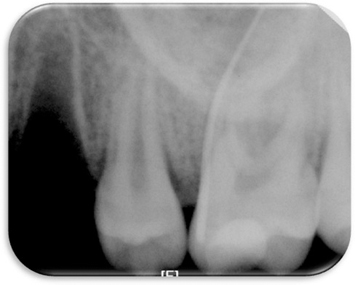

Figure 8

6 month follow up-periapical x-ray.

Figure 8 6 month follow up-periapical x-ray.